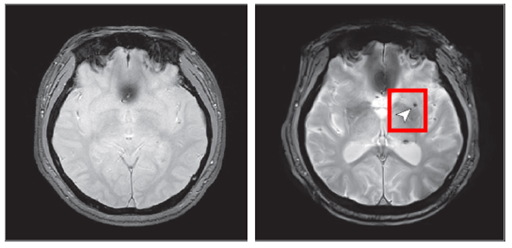

| ▲왼쪽노화 기반 참여 (오른쪽)8년 후 추적조사 참여 (사진=질병관리청 제공) |

[매일안전신문=김진섭 기자] 질병관리청 국립보건연구원이 중등도 이상의 수면무호흡이 뇌 미세출혈의 위험을 높인다는 연구결과를 발표했다.

연구팀은 노화 심층조사사업 참여자 중 중장년층 1,441명을 8년 간 추적하여 수면무호흡의 중증도가 뇌 미세출혈 발생에 미치는 영향을 분석했다.

이러한 결과는 뇌혈관질환 발생 위험과 관련된 특정 유전자 보유 여부와는 상관없는 것으로 나타나, 수면무호흡증 자체가 뇌 미세출혈 발생 위험을 높이는 독립적인 위험 요인임을 확인하였다.